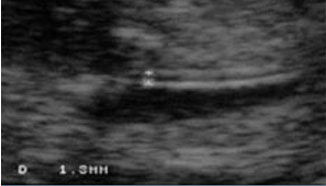

寶寶頸后透明帶為2.9毫米,這個數(shù)值在正常范圍的上限。雖然他的患病風(fēng)險要高于左圖1中的寶寶,但十有八九測量是完全正常的。